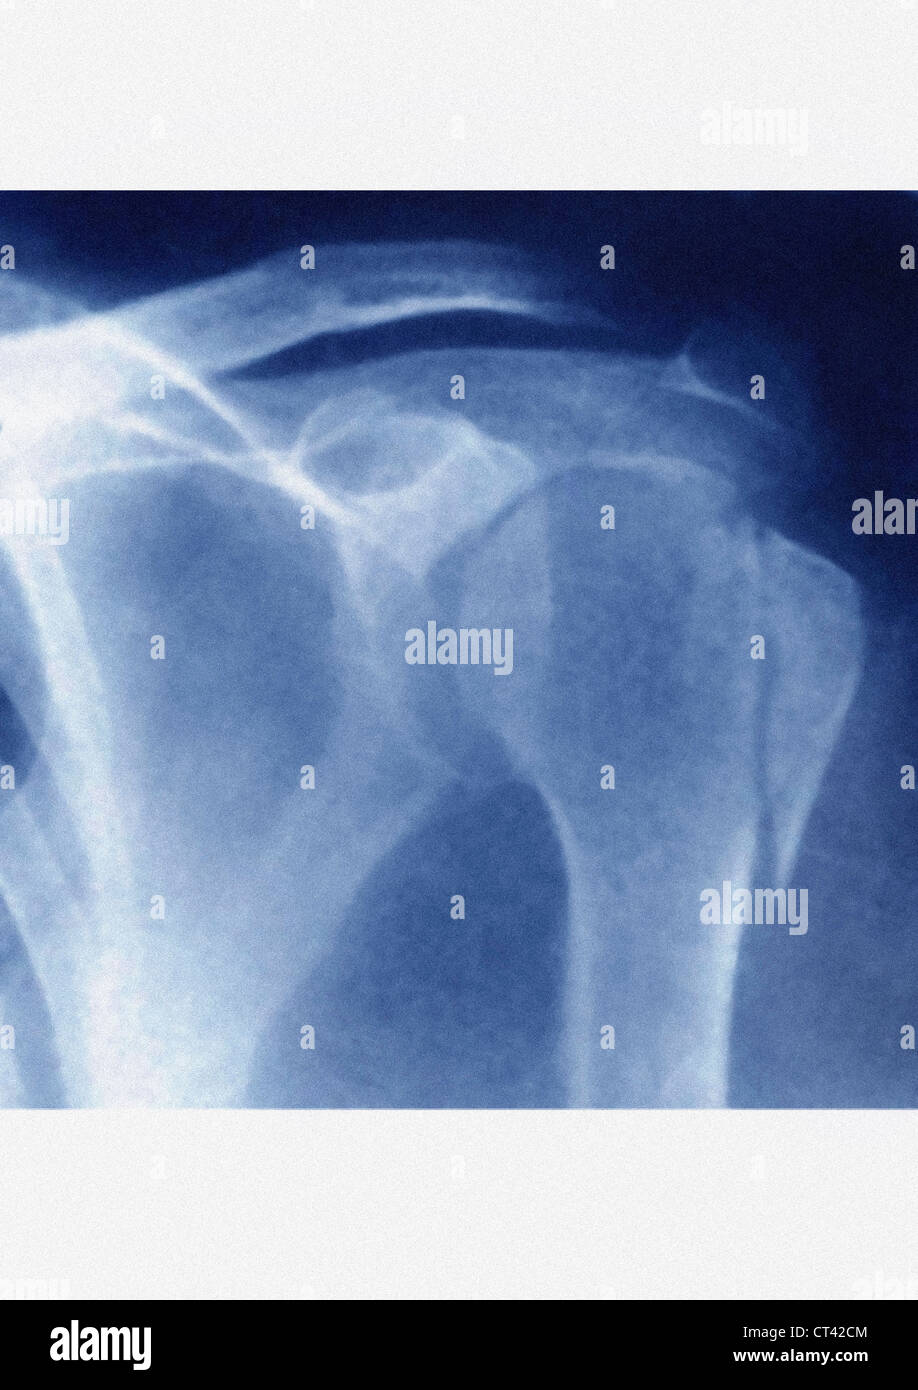

FRACTURED SHOULDER, XRAY Stock Photo Alamy Shoulder Fracture X Ray Soft tissue areas, cortical margins, trabecular patterns,bony alignment, joint. The neer classification of proximal humeral fractures is probably the most frequently used system along with the ao classification of proximal humeral fractures. However, a doctor may request additional imaging, such as a ct. Magnetic resonance imaging (mri) : The shoulder joint is between part of the scapula or shoulder blade. Shoulder Fracture X Ray.

FRACTURED SHOULDER, XRAY Stock Photo Alamy Shoulder Fracture X Ray A recommended systematic checklist for reviewing musculoskeletal exams is: The shoulder joint is between part of the scapula or shoulder blade (blue line) and the proximal humerus (green line). However, a doctor may request additional imaging, such as a ct. Magnetic resonance imaging (mri) : Soft tissue areas, cortical margins, trabecular patterns,bony alignment, joint. The neer classification of proximal humeral. Shoulder Fracture X Ray.